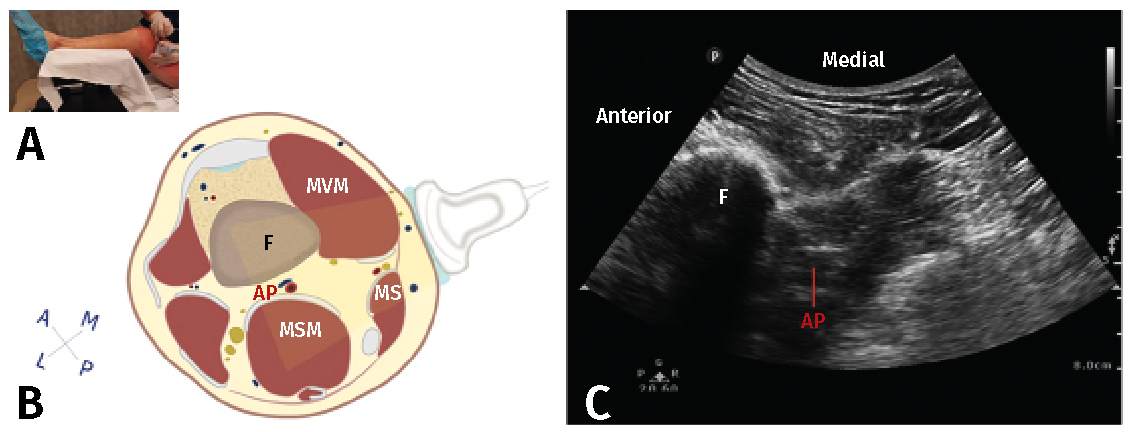

El canal de los aductores contiene, además de los vasos femorales y el nervio safeno, el nervio destinado al vasto medial, el nervio cutáneo femoral medial, el nervio retinacular medial y las ramas articulares distales del nervio obturador(4). Excepto el nervio vasto medial, el resto de los nervios son solo sensitivos y todos representan un papel importante en la inervación sensitiva de la rodilla(1). Tanto el nervio safeno como el nervio del vasto medial contribuyen a la inervación de la cara anteromedial de la rodilla y, por tanto, son dianas importantes en este bloqueo (Figura 4)(11). Dado que salen del canal de los aductores en el tercio distal, el tercio medio del canal es el sitio óptimo para la realización del bloqueo, administrando el anestésico local en ambos nervios mientras se minimiza la posibilidad de difusión proximal al triángulo femoral(12).

Figura 4. Bloqueo del canal de los aductores. A: posición del transductor al nivel del muslo; B: corte anatómico transversal del canal de los aductores; C: visión ecográfica. AF: arteria femoral; MAM: músculo aductor magno; MG: músculo gracilis; MS: músculo sartorio; MVM: músculo vasto medial; NRM: nervio retinacular medial; NSa: nervio safeno, VF: vena femoral(11).

La técnica es sencilla bajo visión ecográfica y tiene la ventaja de tener menor bloqueo motor del cuádriceps que el bloqueo del nervio femoral, aunque el uso de grandes volúmenes de anestésico local puede provocar la migración del mismo hacia porciones más proximales del nervio femoral y, secundario a ello, presentarse también bloqueo motor. En general, este bloqueo se ha popularizado en los últimos años por la menor tasa de complicaciones relacionadas con el bloqueo motor del cuádriceps, permitiendo una deambulación precoz, menor riesgo de caídas, manteniendo igualdad en la calidad analgésica y el consumo de opioides(13). La media de volumen de anestésico local utilizado es de 20 mL.

Un estudio realizado en voluntarios sanos mostró que el bloqueo del canal de los aductores reducía la fuerza del cuádriceps en solo un 8%, mientras que el bloqueo del nervio femoral la reducía en un 49%, sugiriendo, por tanto, que el riesgo de debilidad y caídas es menor con el bloqueo del canal de los aductores(14). Aunque esto puede tener poca relevancia clínica en la recuperación temprana, ya que existen múltiples causas de debilidad del cuádriceps perioperatorias diferentes a los bloqueos regionales, como son la fuerza muscular previa a la cirugía y el manguito de isquemia.